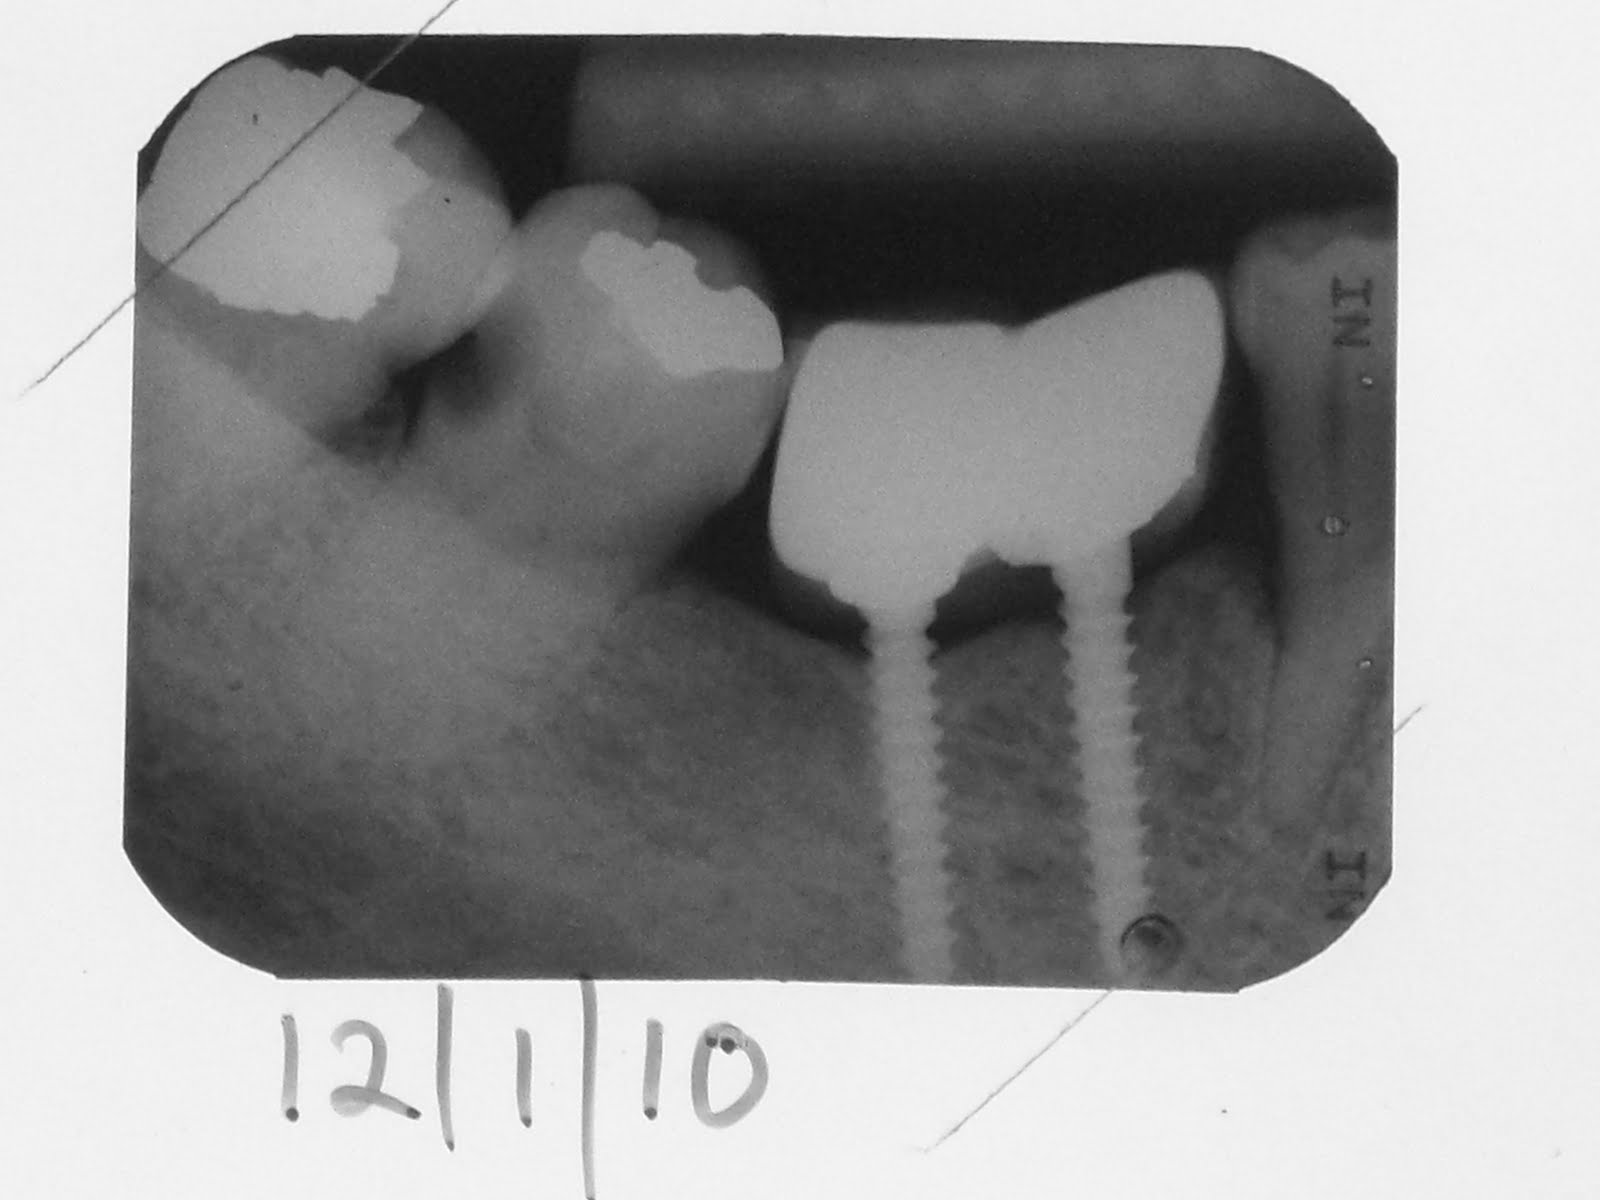

The lower right first molar was extracted and after a short healing period, 2 minis were placed.

A PFM was placed and the patient happily used it for 2 years but came back then to complain of a toothache which he assumed must be due to the implant we placed for him.

An xray showed that the toothache was due to the second molar distal caries. The incidental finding was a very healthy and strong looking cortical bone around the minis. Amazingly also, bone has climbed at least 2 thread widths up the mini dental implant ! Is this, should this be the new standard of care in implant dentistry ?